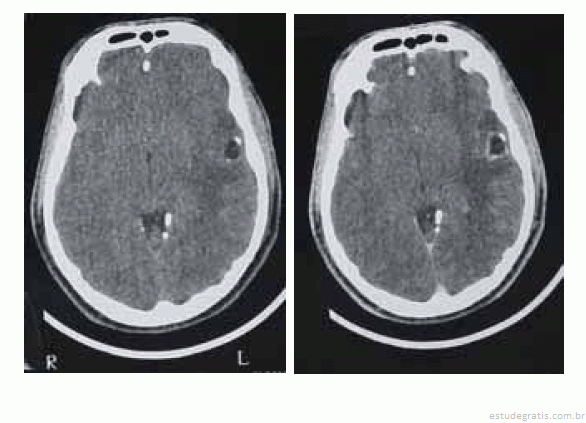

Uma paciente de 35 anos de idade foi levada ao prontosocorro após uma convulsão. Ao exame de admissão, encontravase confusa, sonolenta, porém reativa ao chamado. Apresentava sutil paresia braquiofacial direita. O esposo informou que, nos últimos cinco meses, a paciente começou a apresentar dificuldade para se comunicar, troca de palavras e dificuldade para nomeação. Há duas semanas, o quadro piorou e começou a ficar desligada e a apresentar abalos musculares no membro superior direito, de rápida duração, além de queixar-se de dor de cabeça. Foi realizada uma tomografia computadorizada (TC) de crânio, sem e com contraste, obtendo-se as imagens a seguir.

O eletroencefalograma pode evidenciar atividade delta rítmica intermitente na região temporal esquerda, achado compatível com o quadro clínico.